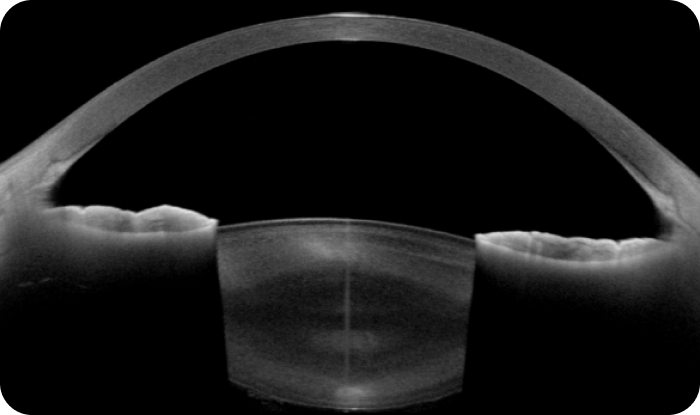

1. 자칫 놓치기 쉬운 백내장 혼탁의 해부학적 정밀 진단

숙련된 안과 전문의의 진찰 소견과 더불어, 닥터 ICL 안과에서는 세극등 현미경의 육안 소견으로 놓칠 수 있는 부분까지 고해상도 CT 촬영장비인 CAISA2(Tomey, Japan) 와 ANTERION(Heidelberg Engineering, Germany)을 이용하여 백내장 혼탁의 위치와 정도를 좀 더 정확하고 입체적으로 파악합니다.

<<ANTERION>>

<<CASIA 2>>

그림 1

그림 2

수정체 부분을 닥터 ICL 안과의 고해상도CT“ANTERION”으로 찍은 모습<그림 2>

(( 그림(1)에서 빨간 색 박스부분이 확대된 모양입니다.))

백내장 수술에 직접적인 영향을 주는 수정체의 앞/뒤주머니(Anterior/posterior capsule), 피질(Cortex), 핵(Nucleus),

수정체 소대의 완전성을 보여주는 수정체 중심축 중심이탈과 기울어짐(Decenteration & Tilt) 등은 물론, 현대 백내장 수술에서

가장 까다로운 수술중 합병증인 홍채이완증후군(Intraoperative Floppy Iris Syndrome, IFIS)을 일으키는Floppy 홍채(Iris)의

두께와 산대정도, 현대 백내장 수술의 백미인  무봉합 미세절개의 설계도 역할을 하는 윤부(Limbus)와 각막(Cornea)

주변부의 위치관계, 수술 후 가장 무서운 합병증인 안압상승, 녹내장과 관련된  공막돌기(Scleral Spur),

섬유주(Trabecular Meshwork)의 해부학적 완전성 등  백내장 수술과 관련된 많은 정보를 얻을 수 있어서,

수술 전 더욱 세밀하고 섬세한 계획을 세워 부작용 없는 수술을 위한 만반의 태세를 갖추고 있습니다.